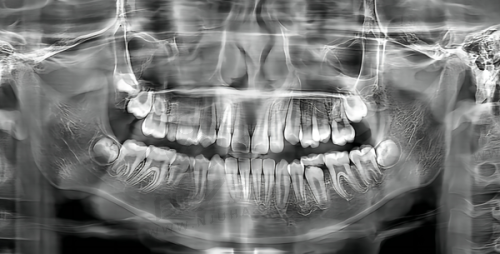

牙齿健康是我们生活中不容忽视的一部分,拥有一口好牙不仅能提升生活质量,还能增添个人自信。然而,在江门台山市,面对众多的牙科医院,许多人会感到困惑:到底哪家牙科医院才是看牙实惠又好的选择呢?别担心,今天就为大家精心推荐台山市看牙技术好、收费实惠的5大正规牙科,让你在呵护牙齿的道路上不再迷茫。

台山博德口腔以其舒适的医院环境和精良的口腔诊疗设备脱颖而出。这里配备了数字化口腔CT等精良设备,能够精细诊断各种口腔问题,为后续的治疗提供坚实的基础。

专精的医生团队:医生们经验多,擅长各类牙齿矫正和种植牙项目。在牙齿矫正方面,他们提供多种矫正方案,无论是传统金属矫正的经济实用,还是隐形矫正的美观舒适,都能满足不同患者的需求。

合理的价格体系:牙齿矫正价格相对合理,传统金属矫正大概在8000 - 12000元左右,隐形矫正则在20000 - 35000元不等。种植牙价格根据种植体品牌不同,在5000 - 15000元/颗。这样的价格区间,让更多人能够享受到优质的口腔治疗服务。